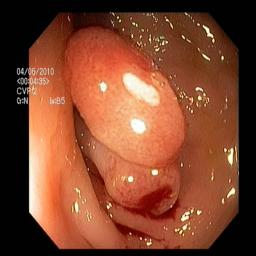

The performance metrics for Edgeconnect and AOTGAN on the validation data after fine-tuning the models, are shown in Table II. In addition to qualitative evaluation, Figure 3 provides example data from the different steps of the PolypConnect pipeline using the EdgeConnect model and the AOTGAN model. Due to obvious visual differences in the generated polyps between the models, we selected the EdgeConnect model as the main polyp inpainting model of the PolypConnect pipeline for further evaluation and qualitative assessment by domain experts.

(a) Refer to caption Refer to caption Refer to caption Refer to caption Refer to caption Refer to caption

(b) Refer to caption Refer to caption Refer to caption Refer to caption Refer to caption Refer to caption

(c) Refer to caption Refer to caption Refer to caption Refer to caption Refer to caption Refer to caption

(d) Refer to caption Refer to caption Refer to caption Refer to caption Refer to caption Refer to caption

(e) Refer to caption Refer to caption Refer to caption Refer to caption Refer to caption Refer to caption

(f) Refer to caption Refer to caption Refer to caption Refer to caption Refer to caption Refer to caption

(g) Refer to caption Refer to caption Refer to caption Refer to caption Refer to caption Refer to caption

(h) Refer to caption Refer to caption Refer to caption Refer to caption Refer to caption Refer to caption

Figure 3: Sample data used and generated in the different steps of PolypConnect pipeline. (a) - real polyp images, (b) - manually annotated polyp masks, (c) - randomly selected colon images used as input to the final step of PolypConnect, (d) - extracted edge images of row c. (e) - extracted edge images of polyp regions of row a using the masks of row b. (f) - combined edge images of row d and f. (g) - generated polyp on the images of row c using EdgeConnect. (h) - generated samples from AOTGAN.